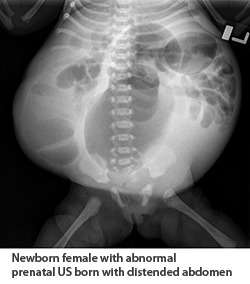

Kidney, ureter, and bladder (KUB) test findings can usually be used for diagnosis based on the typical appearance of the bowels hanging over the lateral edge of the abdominal wall. Enlarged bladder